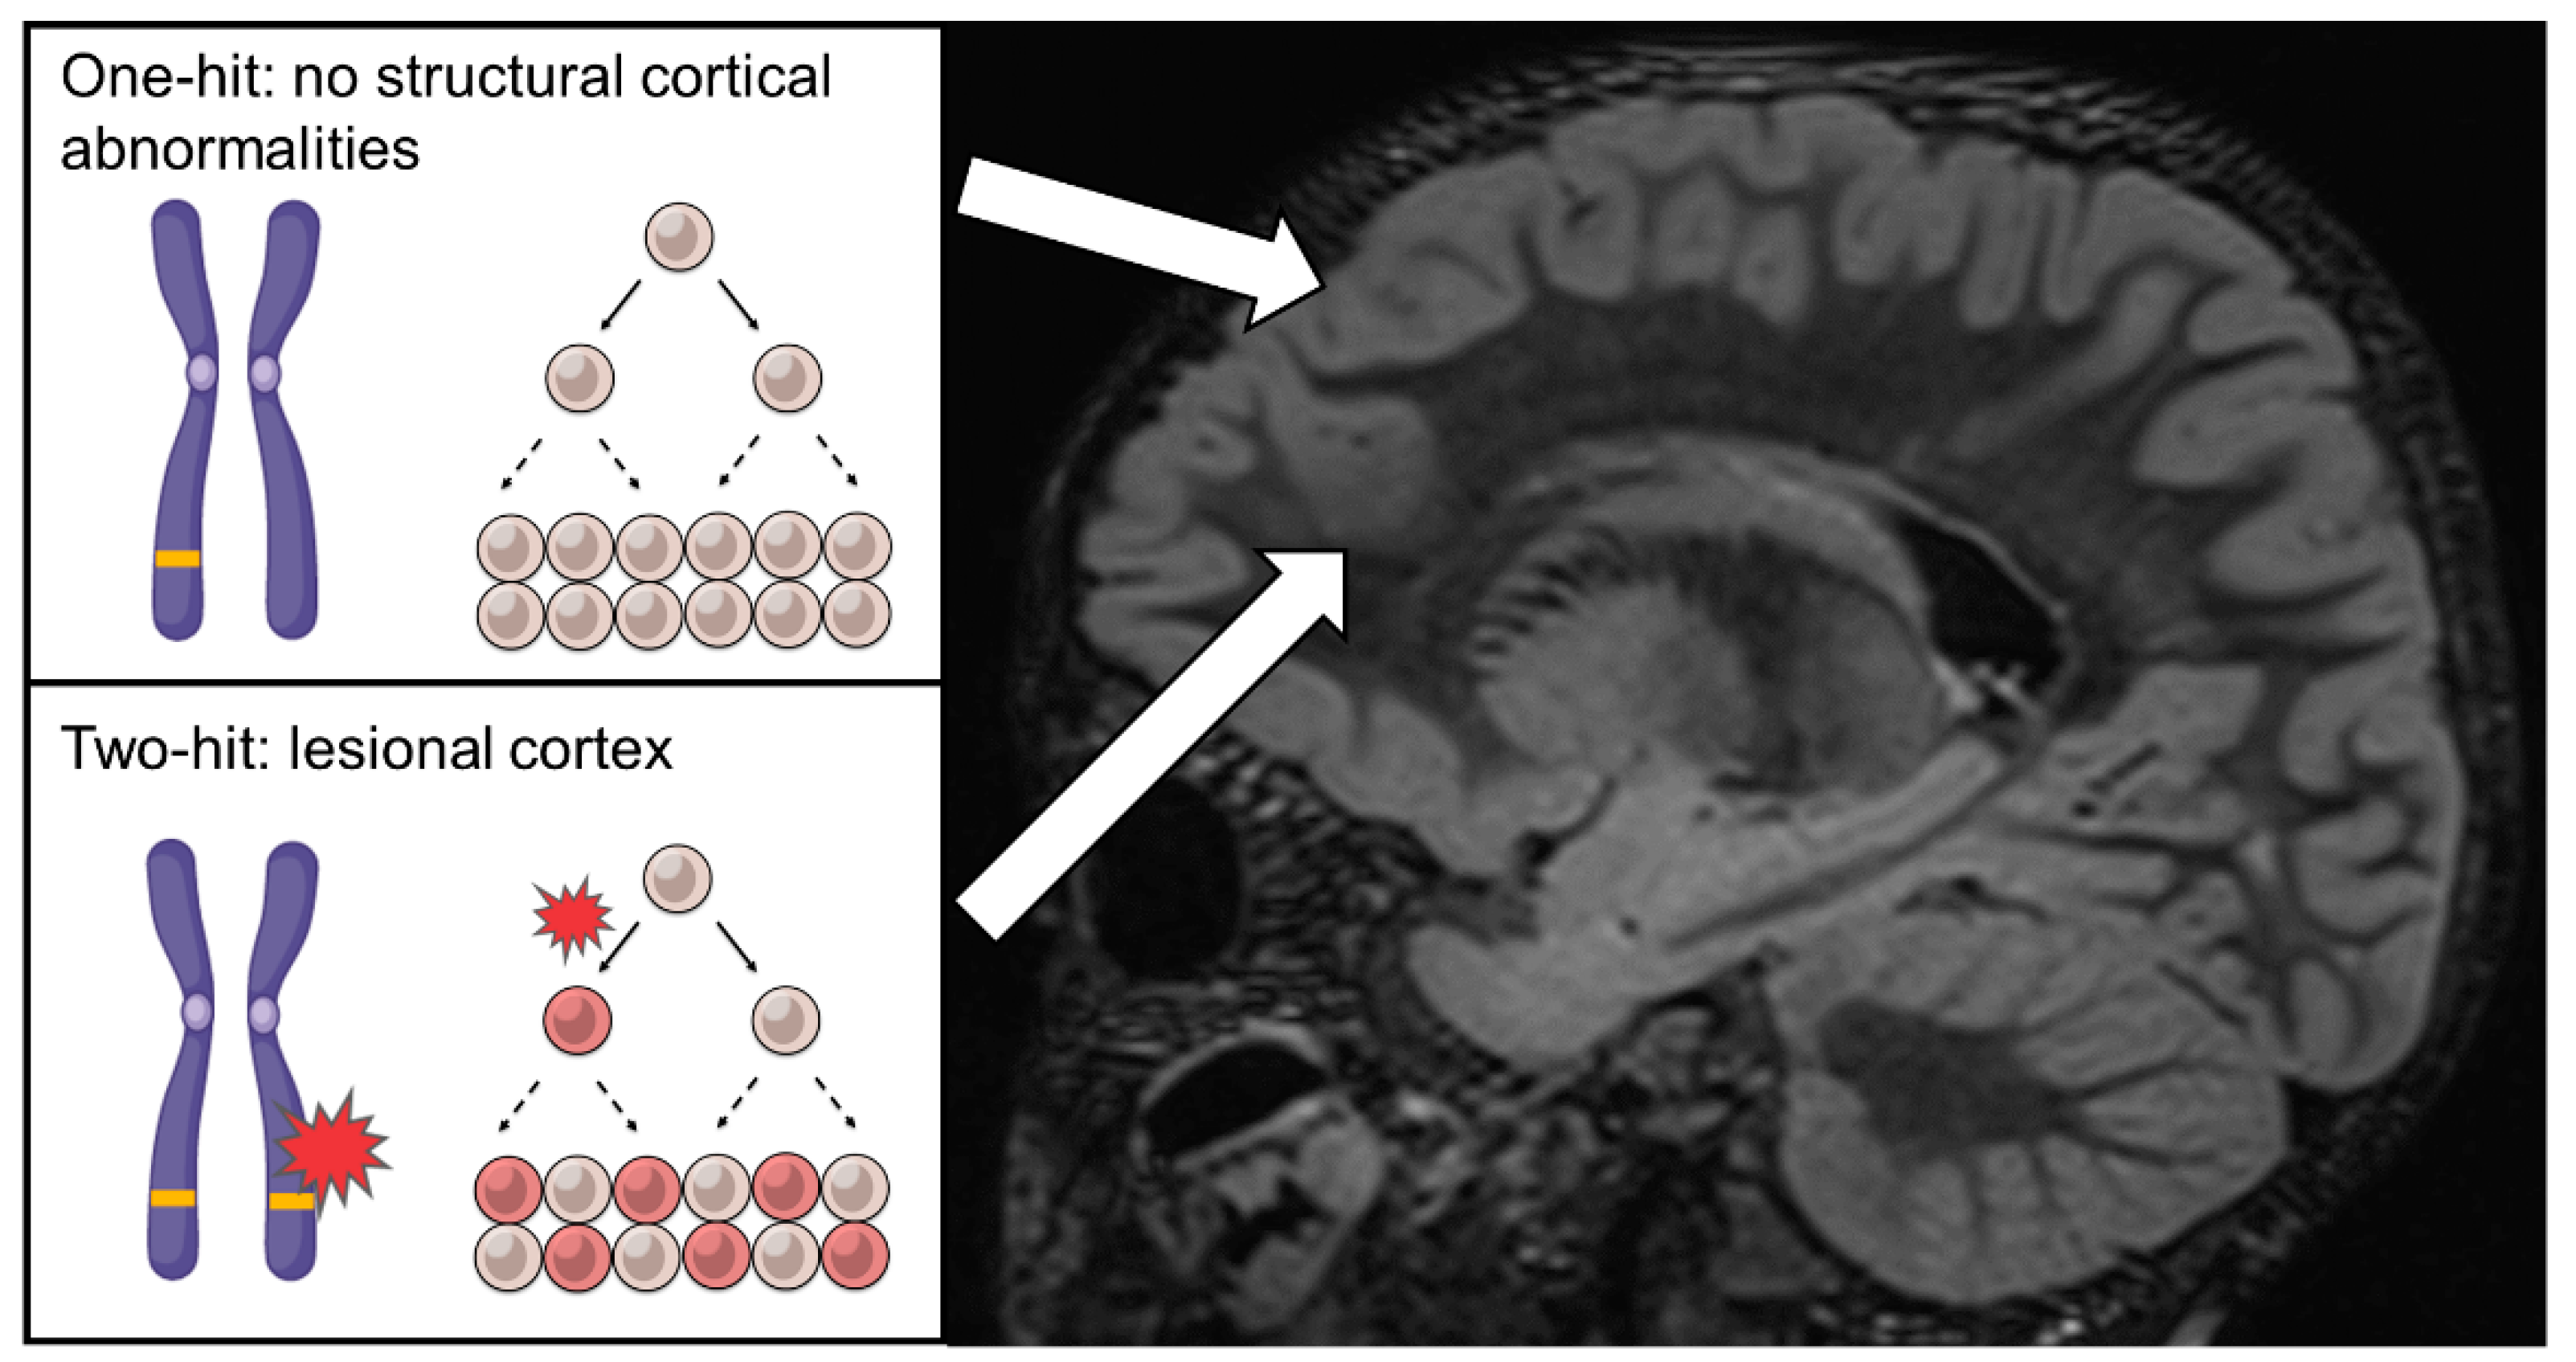

4. The Curious Cases of Familial FCD, Non-Lesional Epilepsy and the Two-Hit Hypothesis—2014

- Leventer, R.J.; Jansen, F.E.; Mandelstam, S.A.; Ho, A.; Mohamed, I.; Sarnat, H.B.; Kato, M.; Fukasawa, T.; Saitsu, H.; Matsumoto, N.; et al. Is focal cortical dysplasia sporadic? Family evidence for genetic susceptibility. Epilepsia 2014, 55, e22–e26. [Google Scholar] [CrossRef] [PubMed]

- Dibbens, L.M.; de Vries, B.; Donatello, S.; Heron, S.E.; Hodgson, B.L.; Chintawar, S.; Crompton, D.E.; Hughes, J.N.; Bellows, S.T.; Klein, K.M.; et al. Mutations in DEPDC5 cause familial focal epilepsy with variable foci. Nat. Genet. 2013, 45, 546–551. [Google Scholar] [CrossRef]

- Ishida, S.; Picard, F.; Rudolf, G.; Noe, E.; Achaz, G.; Thomas, P.; Genton, P.; Mundwiller, E.; Wolff, M.; Marescaux, C.; et al. Mutations of DEPDC5 cause autosomal dominant focal epilepsies. Nat. Genet. 2013, 45, 552–555. [Google Scholar] [CrossRef]

- Scheffer, I.E.; Heron, S.E.; Regan, B.M.; Mandelstam, S.; Crompton, D.E.; Hodgson, B.L.; Licchetta, L.; Provini, F.; Bisulli, F.; Vadlamudi, L.; et al. Mutations in mammalian target of rapamycin regulator DEPDC5 cause focal epilepsy with brain malformations. Ann. Neurol. 2014, 75, 782–787. [Google Scholar] [CrossRef]

- Knudson, A.G. Two genetic hits (more or less) to cancer. Nat. Rev. Cancer 2001, 1, 157–162. [Google Scholar] [CrossRef]

- Baulac, S.; Ishida, S.; Marsan, E.; Miquel, C.; Biraben, A.; Nguyen, D.K.; Nordli, D.; Cossette, P.; Nguyen, S.; Lambrecq, V.; et al. Familial focal epilepsy with focal cortical dysplasia due to DEPDC5 mutations. Ann. Neurol. 2015, 77, 675–683. [Google Scholar] [CrossRef]